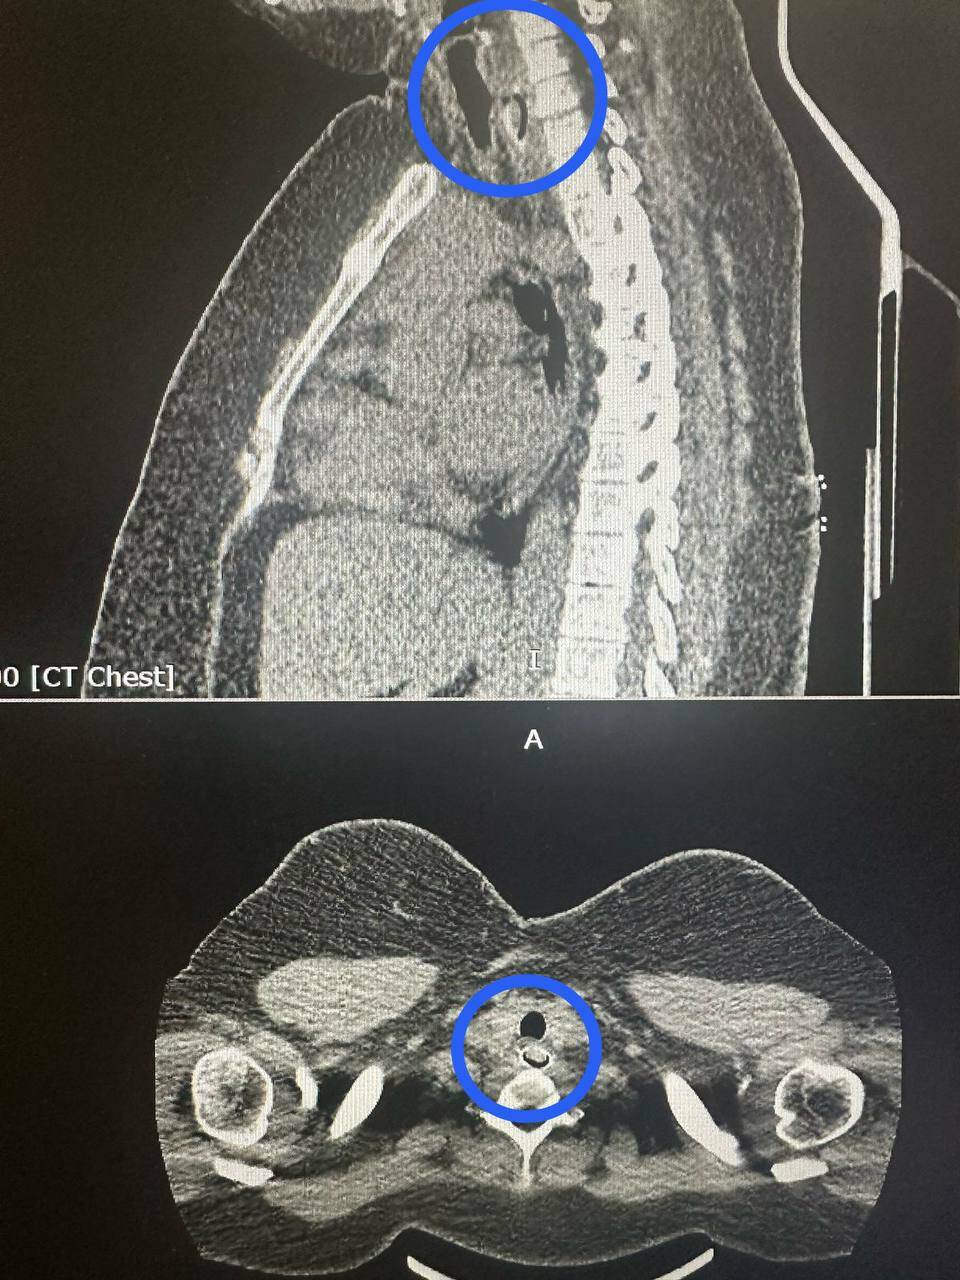

Компьютерная томография показала, что косточка перекрыла почти весь просвет пищевода. Достать ее через рот было невозможно. Поэтому хирурги сделали разрез в области шеи и пищевода, чтобы аккуратно убрать инородное тело.

Фото: РКБ Татарстана